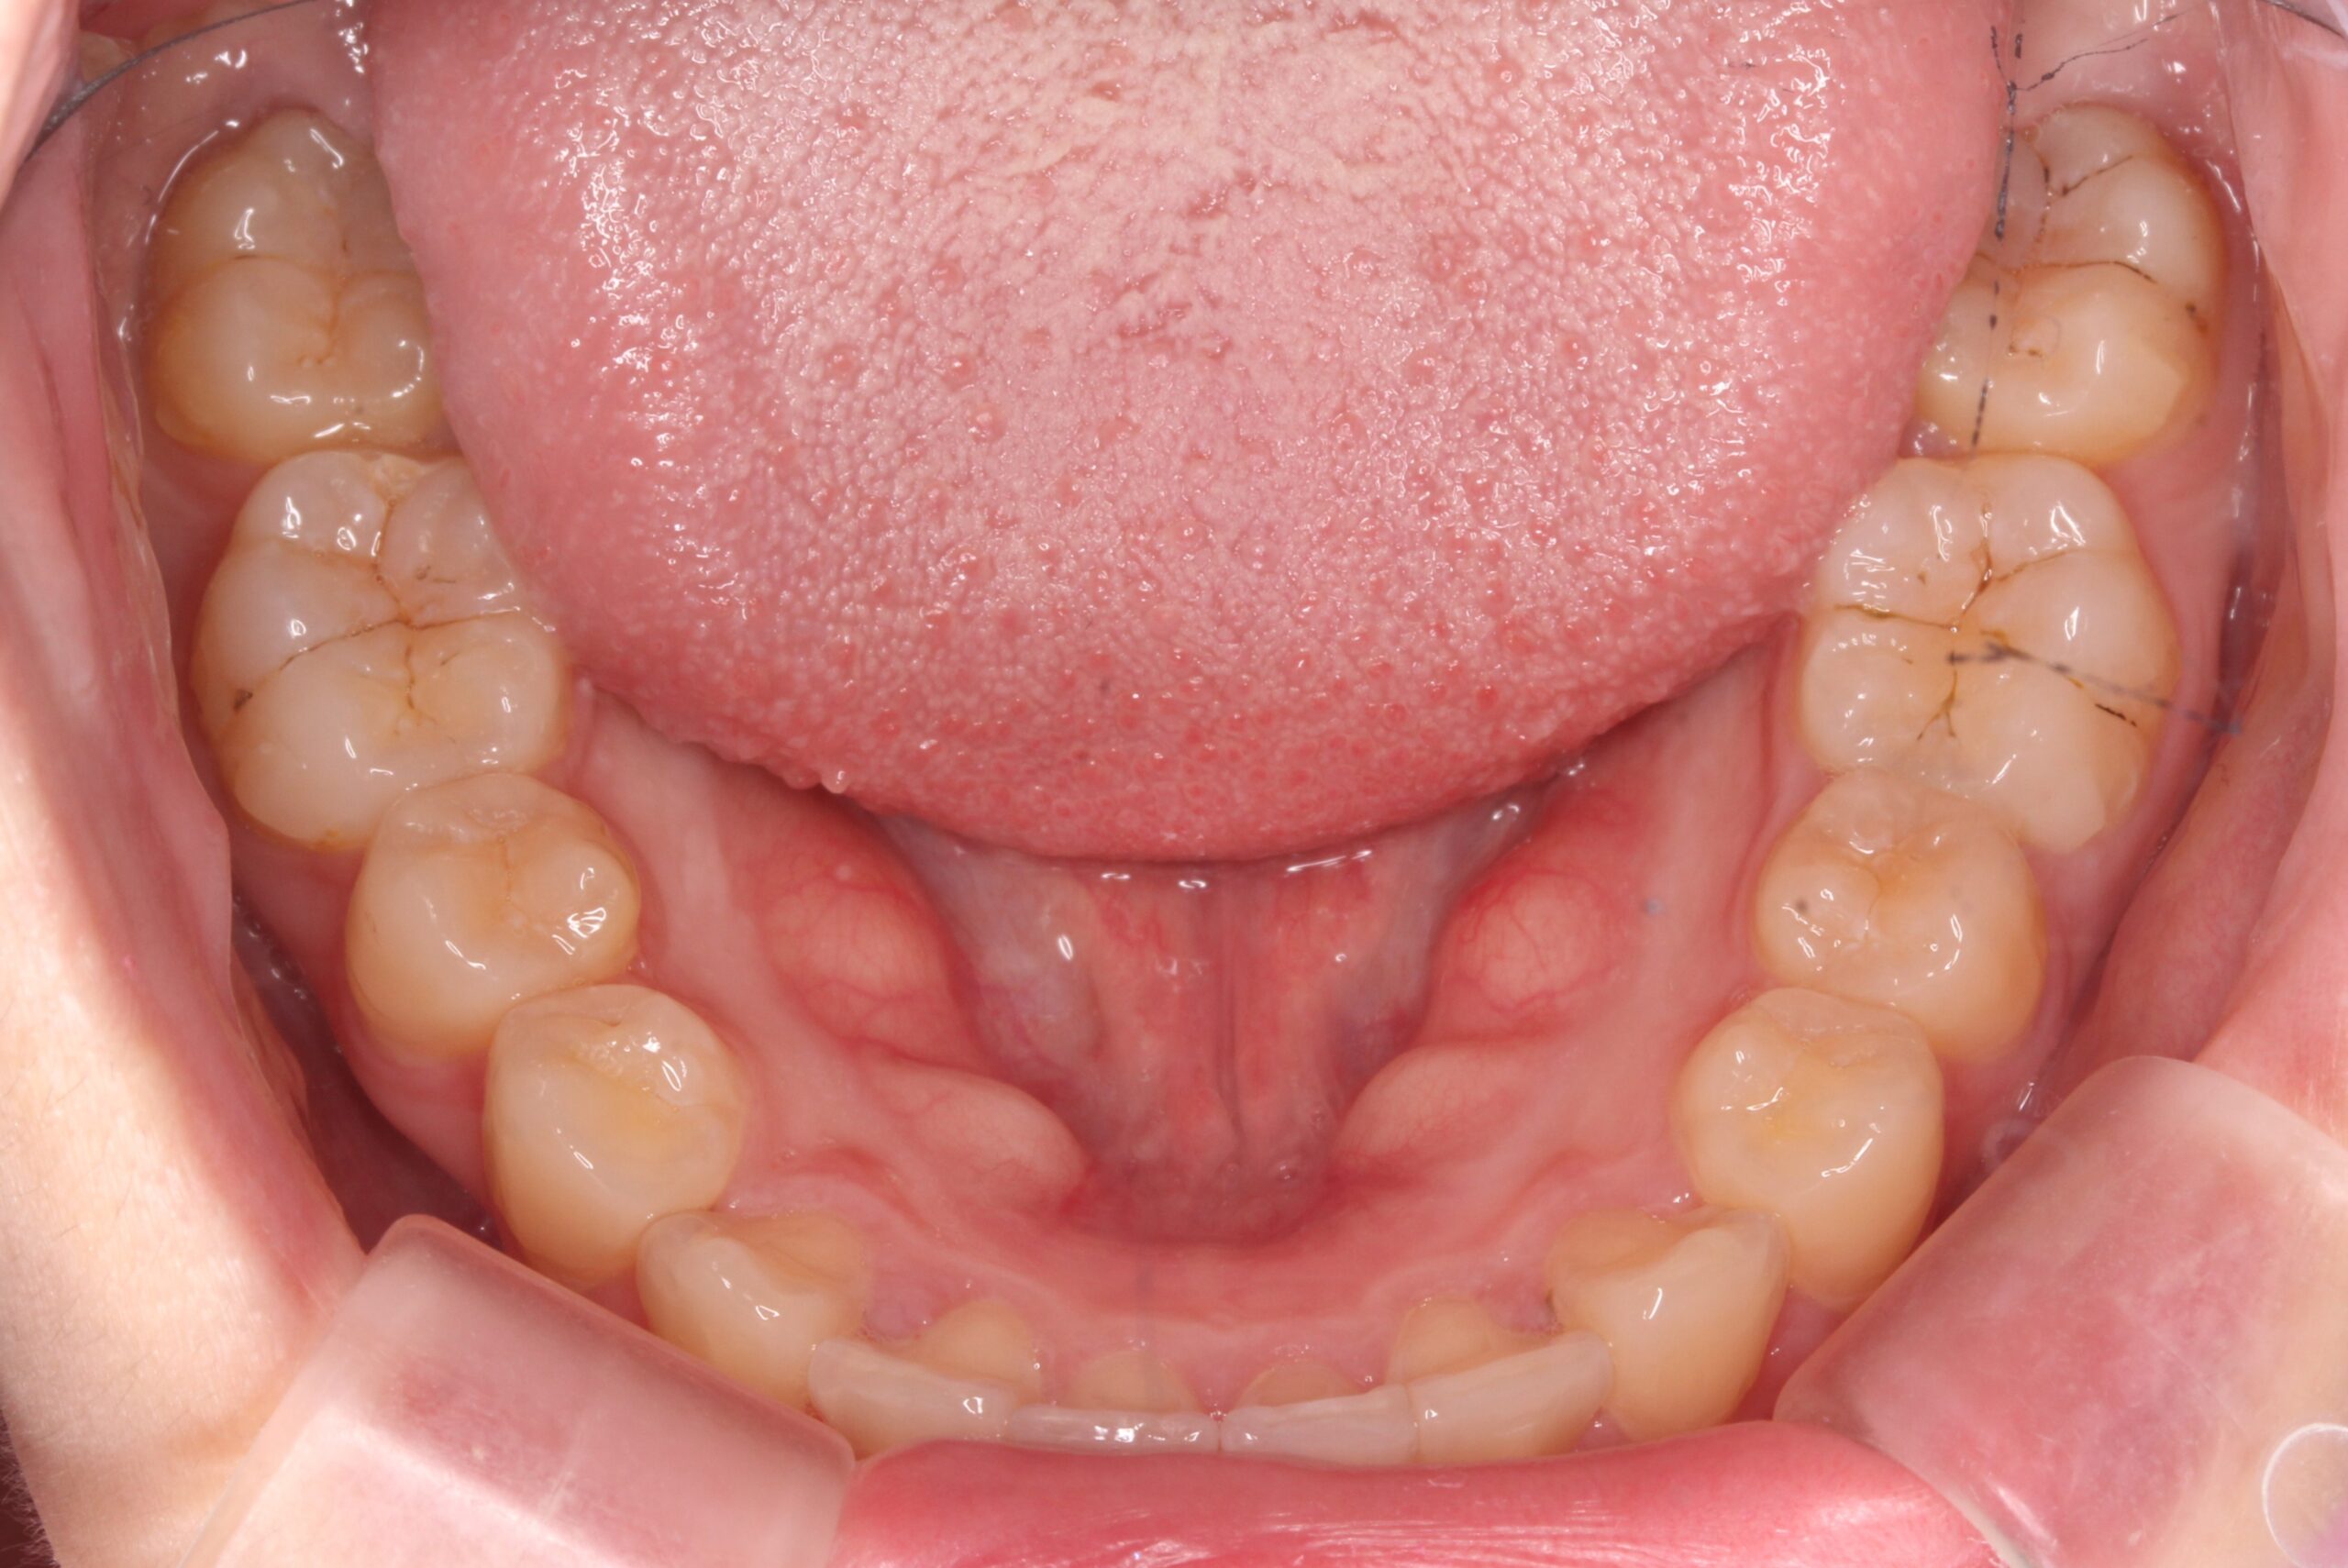

矯正術前:下顎

矯正術後:下顎